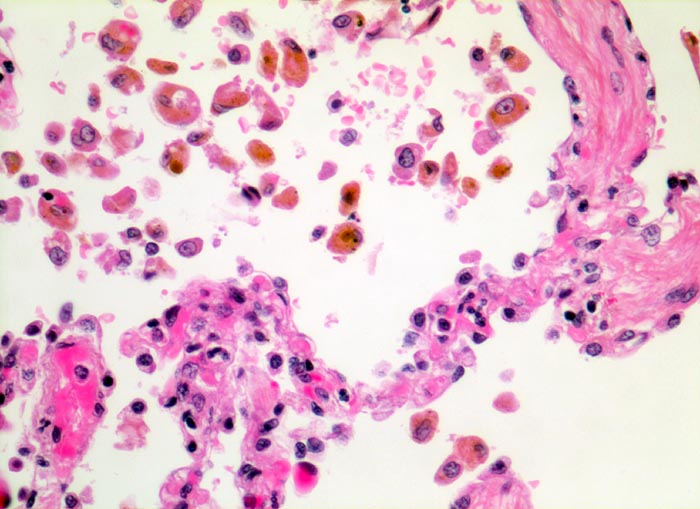

In einer frühen Phase kommt es zur roten Stauungsinduration, welche in eine braune Stauungsinduration übergeht. Die Eindrückbarkeit der Lungen ist aufgrund der Fibrosierung der Alveolarsepten vermindert. Die meist fleckförmige braune Verfärbung beruht auf der Anhäufung von hämosiderinhaltigen Herzfehlerzellen in den Alveolarlichtungen. Makrophagen in den Alveolarlichtungen phagozytieren die ausgetretenen Erythrozyten. Der Nachweis von Erythrozyten im Zytoplasma von Makrophagen spricht für eine frische Blutung. Nach 3-5 Tagen ist in den Makrophagen Hämosiderin nachweisbar. Das Hämosiderin lässt sich mittels Eisenfärbung (Berliner-Blau) zuverlässig von Staubpigment abgrenzen. Als sicheres Zeichen für eine ältere Blutung gelten >20% hämosiderinspeichernde Makrophagen in der bronchoalveolären Lavage (BAL). Die hämosiderinhaltigen Alveolarmakrophagen werden auch Herzfehlerzellen genannt, da sie gehäuft im Rahmen einer linkskardialen Stauung bei Mitralklappenstenose auftreten.

Morphologische Merkmale:

• Mediahypertrophie der Pulmonalvenen.

• Fibrosierung und Verdickung der Alveolarsepten.

• Siderinhaltige Alveolarmakrophagen (=Herzfehlerzellen).